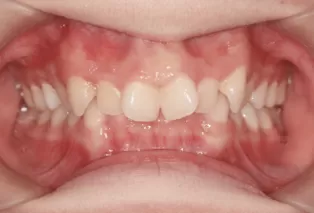

Female, aged 20. Chief complaint: Teeth misalignment, crowded maxillary anterior teeth.

Closed deep bite of anterior teeth, moderate crowding of upper and lower teeth, general facial profile.

Intraoral photos